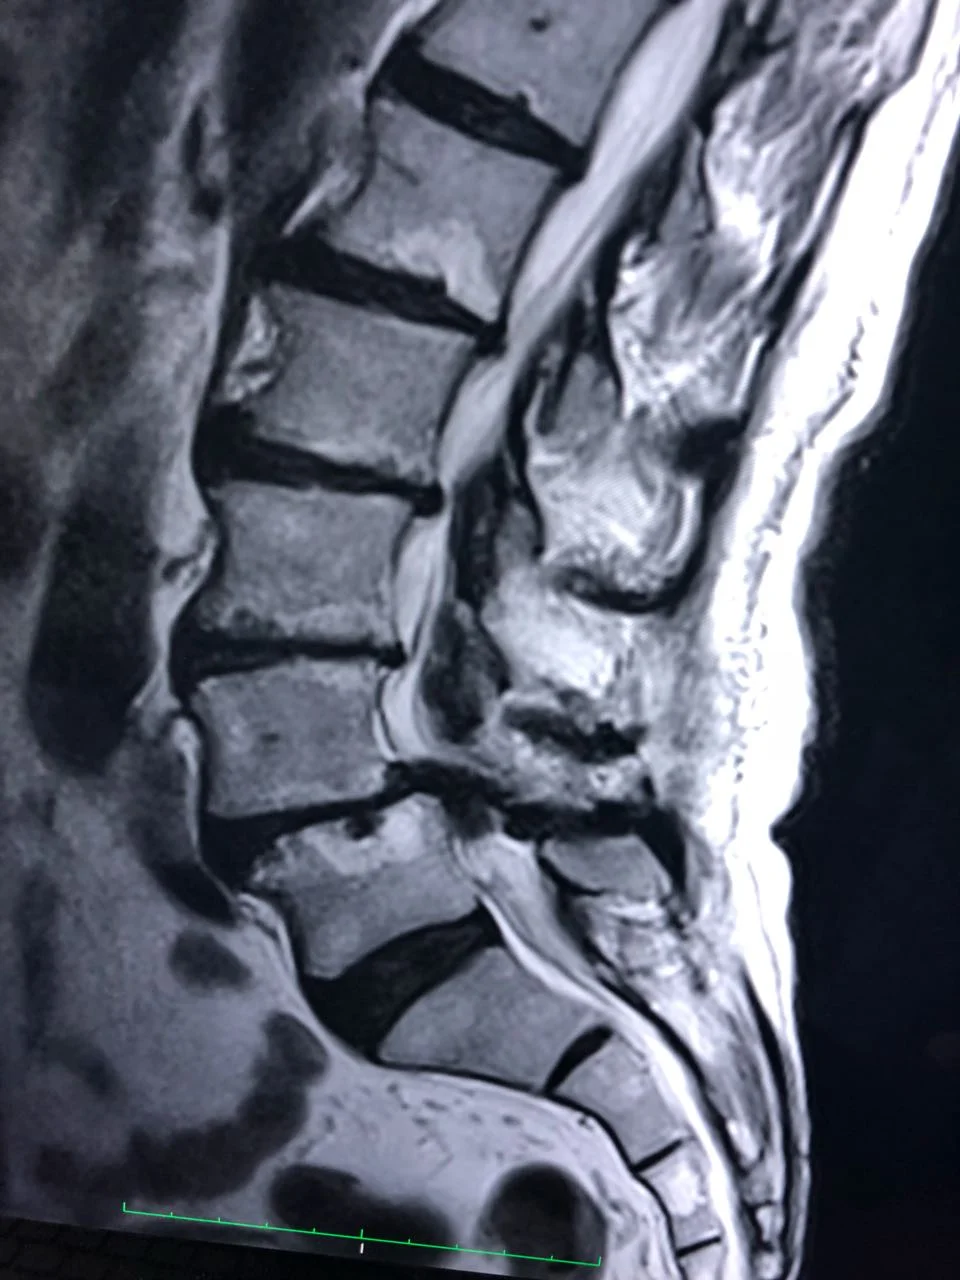

Escoliosis degenerativa lumbar

TRATAMIENTO MEDICO, CONSERVADOR, QUIRURGICO.

COLUMNA VERTEBRAL

MÉDULA ESPINAL